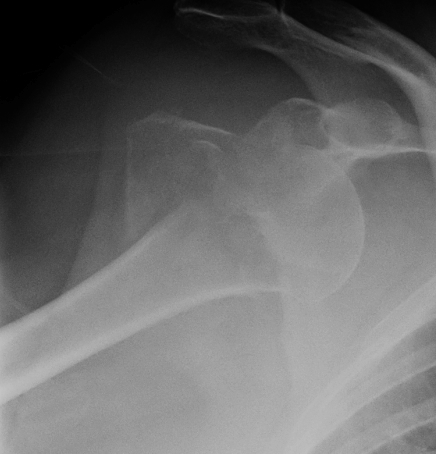

Rotator Cuff Tear

Infraspinatus and supraspinatus wasting after shoulder dislocation in 50 year old

More common in older patients with shoulder dislocation

- 66 patients > 50 with shoulder dislocation

- 60% rotator cuff tear on MRI